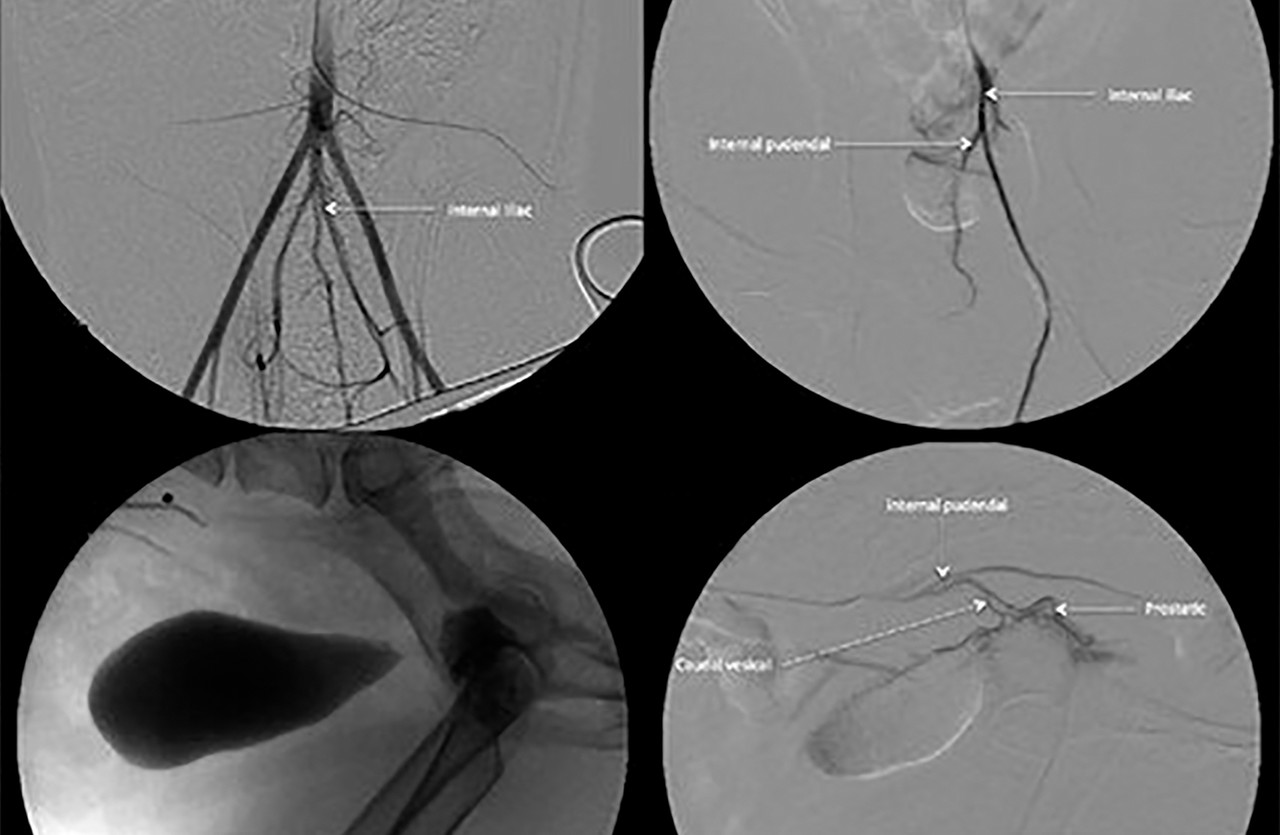

동맥내 항암요법 (IAC)

동맥내 항암요법은 종양 부위에 직접적으로 항암제를 주입하는 방법으로, 일반적인 항암요법에 부작용이 심하거나 효과가 낮은 경우에 적용할 수 있습니다.

이 암치료법은 방광암, 전립선암, 안내암과 같이 항암치료에 반응이 낮은 종양에 주로 적용됩니다.

치료 반응에 따라서 3-4주 간격으로 최대 5회 시술합니다.

• IAC를 통해 기대할 수 있는 효과

1. 일반적인 약물항암치료에 반응이 낮은 종양에 적용할 수 있습니다. (방광암, 전립선암, 비강암, 안내암)

2. 약물항암 대비 항암효과가 높고 부작용이 적습니다.

• IAC는 어떤 아이들에게 적용할 수 있을까요?

1. 약물항암제에 반응이 낮은 경우

2. 약물항암제에 부작용이 심한 경우